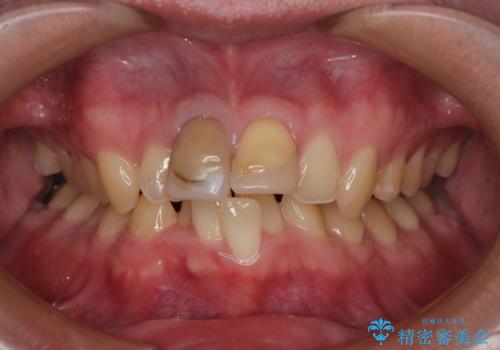

- 以前、保険診療で治療を受けた前歯の見た目が気になるとのことで来院された患者様です。

転倒時に前歯2本が折れてしまい、すでに根管治療(神経の治療)が行われている状態でした。

診査の結果、噛み合わせが深い「ディープバイト」の状態であり、下の前歯には叢生(歯並びのデコボコ)も認められました。